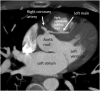

Atherosclerotic Coronary Artery Disease in a Younger Adult With Transseptal Anomalous Left Coronary Artery

We present a case of extensive coronary atherosclerotic disease in a younger patient with an anomalous left coronary artery with transseptal course and show the utility of multimodality evaluation to determine the culprit lesion in patients presenting with this rare association. (Level of Difficulty: Intermediate.).